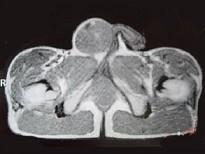

29岁男性患者,右侧睾丸肿痛5个多月,行MRI检查,如图所示,T1加权见右侧阴囊内见球形肿块,呈中等信号,其内信号不均,T2加权肿块为高信号,最可能的结果...

问题 29岁男性患者,右侧睾丸肿痛5个多月,行MRI检查,如图所示,T1加权见右侧阴囊内见球形肿块,呈中等信号,其内信号不均,T2加权肿块为高信号,最可能的结果是()

选项 A.精原细胞瘤 B.睾丸结核 C.畸胎瘤 D.皮样囊肿 E.畸胎癌

答案 A